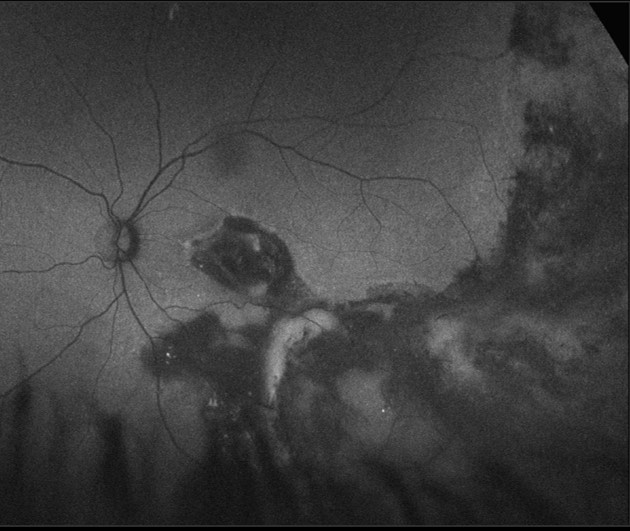

OCT imaging typically shows subtle intraretinal edema or subretinal fluid. OCTA and fluorescein angiography show vascular abnormalities (telangiectatic vessels) with bulb-like aneurysms. Capillary dropout and areas of retinal non-perfusion may also be seen.

A 29 year old Caucasian female with recent onset flashes and floaters, diagnosed with eye disease in her left eye at the age of 13. Her visual acuity in the left eye was counting fingers at 50cm.

More infoRed-free image (left eye)